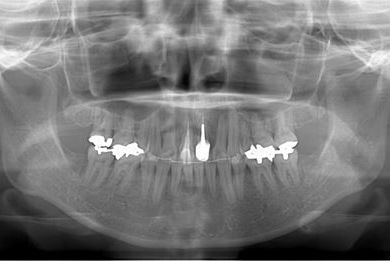

全顎矯正治療+セラミック治療

| 治療方針 | 上下歯牙がだいぶ前にでていて口が閉じづらい状態でした。なるべく金属が入っている歯を抜歯したいので、上下左右第二小臼歯を抜歯して、その隙間を利用して、口元をさげていきました。また、口元を最善の状態にうるために、抜歯スペースを使用したあと、上下左右のインプラントアンカー(釘)でより一層口元を後ろにさげていきました。ただの抜歯ケースよりだいぶ口元が下がっているのが分かります。抜歯したスペースががたつき(叢生量)で使用してしまう場合には、このような方法でより口元をさげることができます。お顔立ちがとてもよくなりました。とても協力していただけたので、しっかりと良くなることができました。 | ||||||||||||||||||||||||||||||||

| 治療内容 | 唇側矯正(ホワイト・上下左右第二小臼歯抜歯・上下インプラントアンカー)、オールセラミッククラウン1本(オールセラミック用土台1本)、ジルコニアフレームオールセラミッククラウン1本 | ||||||||||||||||||||||||||||||||

| 治療期間 | 2年5ヶ月 |